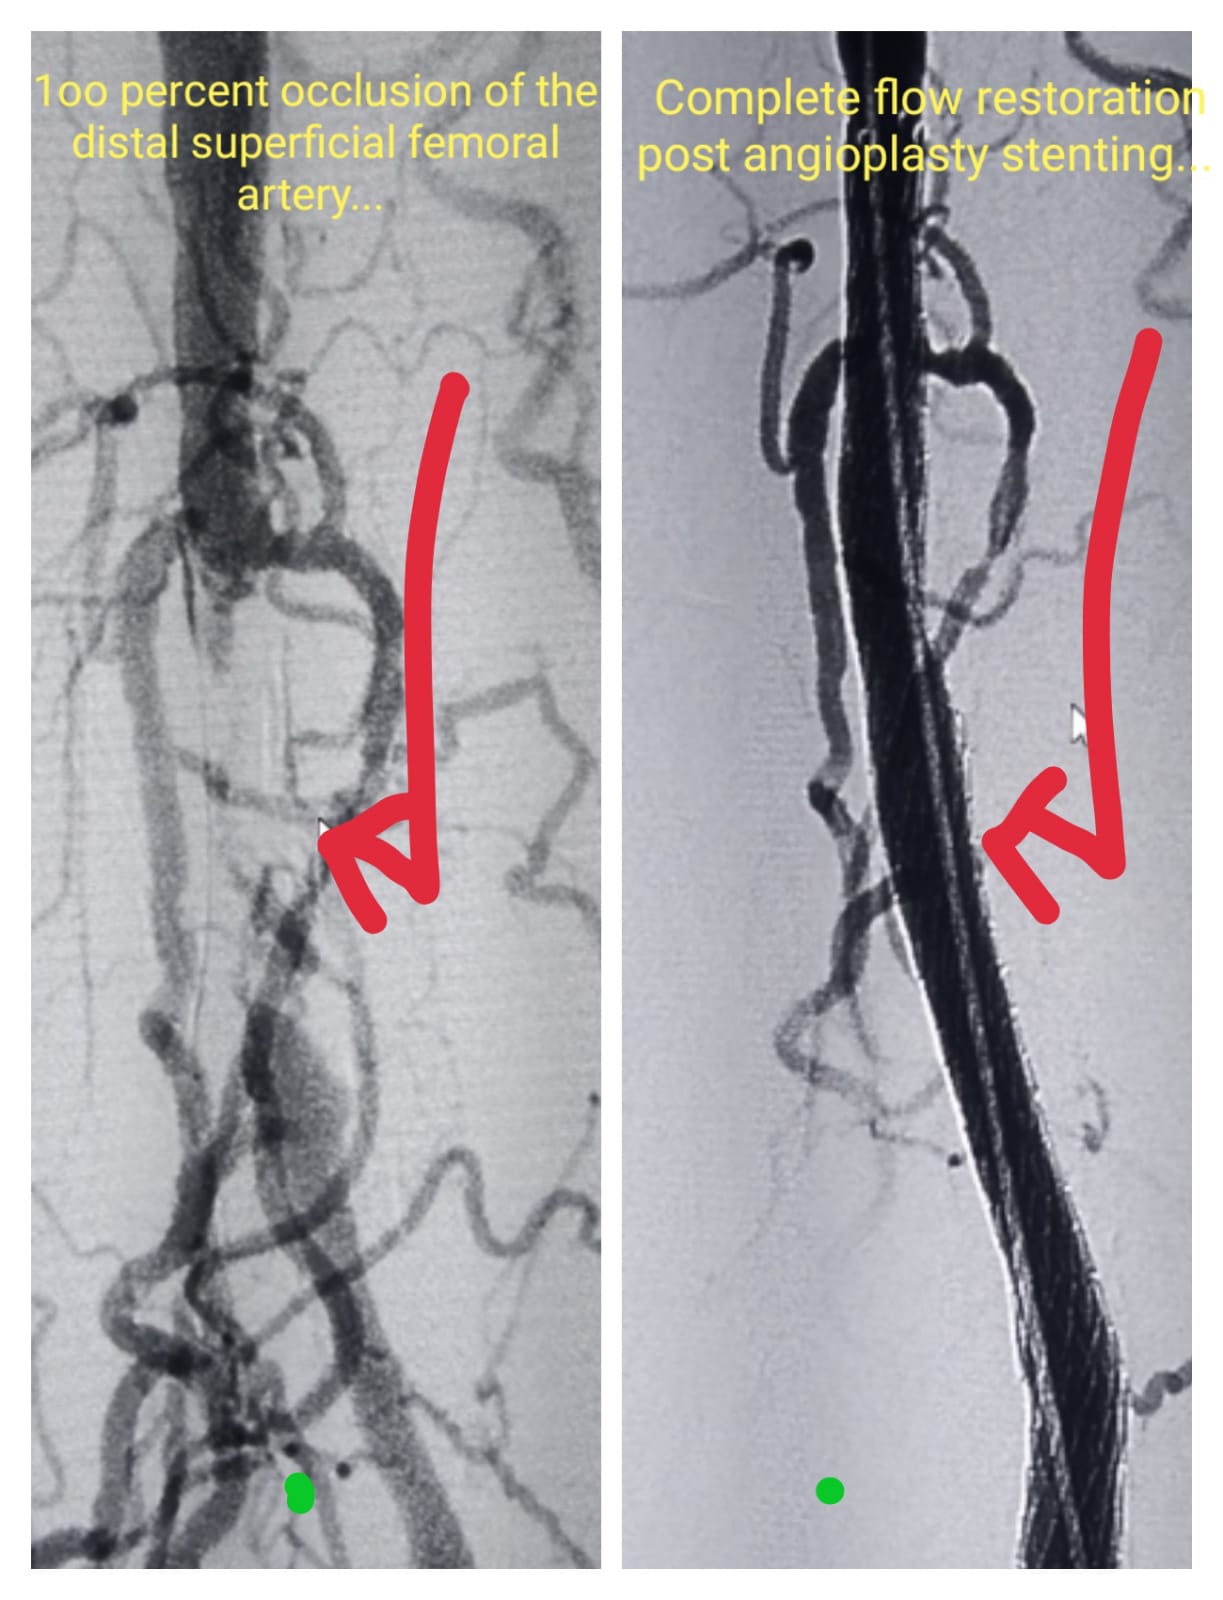

Superficial Artery stenting- Pre Procedure & Complet blood flow restoration post stenting